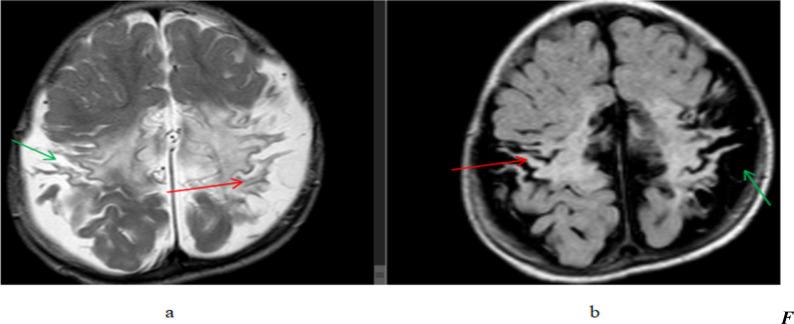

A total of 164 patients were included in this study of which 95(57.9%) were male and 69(42.1%) female patients were seen. A total of 120 patients (73.2%) showed abnormal brain MRI studies. Previous neurovascular insults were the most common abnormalities seen in 75(45.7%) patients followed by imaging findings of congenital and developmental abnormalities seen in 20(12.2%) patients.

本研究共纳入 164 例患者,其中男性 95 例(57.9%),女性 69 例(42.1%)。共有 120 例(73.2%)患者的脑部 MRI 检查结果异常。最常见的异常是既往神经血管损伤,见于 75 例(45.7%)患者,其次是先天性和发育性异常的影像学表现,见于 20 例(12.2%)患者。